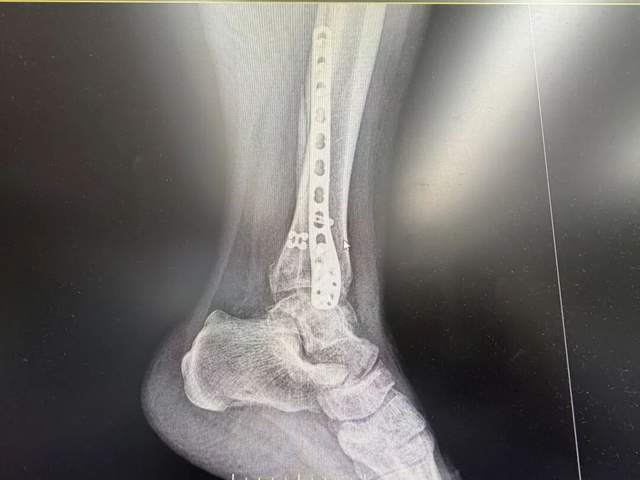

术前术后影像对比

02-右侧腓骨远端骨折切开复位内固定术

采用微创切口,植入钛合金钢板螺钉,确保骨折端精准对位。尹绍猛解释:“腓骨是踝关节的‘支柱’,必须牢固固定才能避免后期力线异常。”

03-下胫腓联合分离袢钢板内固定术

创新使用弹性袢钢板固定胫腓联合,既维持稳定性,又保留生理微动,减少术后僵硬风险。

阶段三(1-3个月):肌力与平衡重建,利用抗阻带、平衡垫逐步增强下肢力量;复查X光显示骨折线模糊,内固定位置良好。